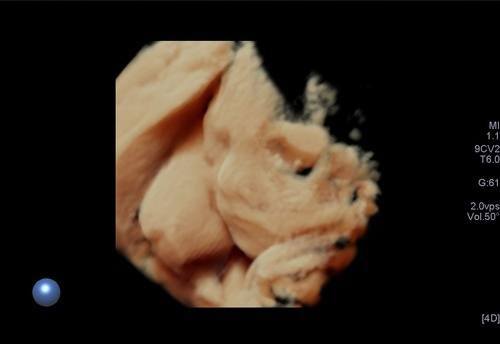

3/4 boyutlu ya da renkli ultrason olarak adlandırılan inceleme ise bebeğin yüzü ya da vücudunun bir kısmının (kollar, bacaklar, eller,ayaklar gibi ) görüntülenmesi anlamına gelir. Bu incelemenin tanısal bir katkısı olmamakta olup daha çok anne, baba ve yakınları için hatıra için yapılmaktadır.